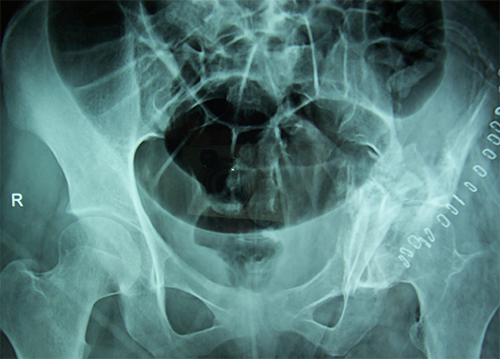

Case:4 GCT Acetabulum

Orthopedic Oncology Doctor|Spine Surgeon Best In Rajasthan

Pre-Op

Best spine surgeon in ahmedabad|Best Trauma Surgeon

Post-Op Scraooing + B.G